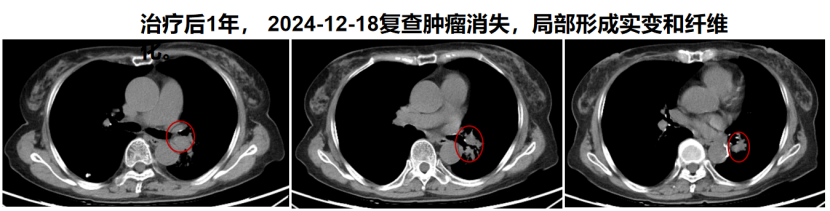

病例三:王某某,女,69岁,新疆昌吉。诊断:1. 左肺恶性肿瘤 小细胞癌 cT3N2M1b IVA期(广泛期)KPS评分:90分;2. 肝转移癌。患者于2023-08体检发现左肺上叶软组织团块,肝左叶内下段转移结节;2023-10-31穿刺活检证实小细胞癌,Ki-67(80%+)。2023-12-20至2024-01-16患者于我院接受重(碳)离子放射治疗;于2023-12-25至2023-12-27接受肝脏转移灶的重(碳)离子放射治疗;同时接受预防性脑照射治疗;于2023-12-14至2023-12-17及2024-01-04至2024-01-07接受2周期EP方案同步化疗。截至2026年3月16日患者状况良好。

【病例提供医生:杨钰玲 科室:放疗中心一科(国际一部)】